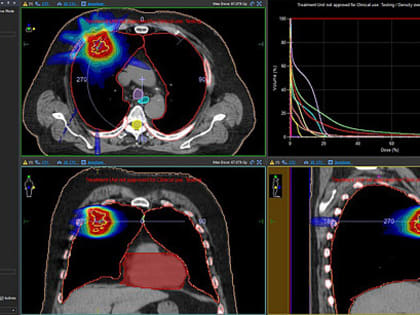

Стереотаксическая терапия: в онкоцентре Кирова внедрён инновационный метод лечения

В рамках национального проекта «Здравоохранение» Центр оснащен четырьмя современными линейными ускорителями, обеспечивающими радиотерапию.